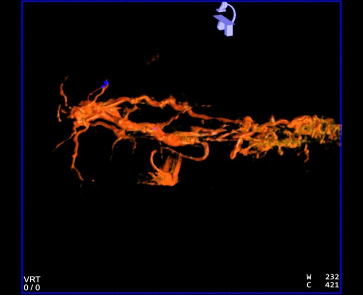

CBCT 扫描血管重建可见,血管迂曲及靶病灶大小和位置

此次术中 DiaSphere®加载的药物是表柔比星,比较直观的感受就是载药速率非常快, 5min 可达 95%以上,明显缩短术中载药时间,节约手术时间,提升了医生的效率。据悉, 该款微球产品亦可加载其他蒽环类化疗药(如:吡柔比星和多柔比星)和伊立替康,可应用 于原发性肝癌和转移性肝癌。其次,DiaSphere®悬浮均匀,术中非常容易地通过科睿驰公 司配套 2.0Fr 微导管“智鹏”的推注,推注阻力并不大,术后复查 DiaSphere®在靶病灶内 部均匀沉积,栓塞效果良好(科睿驰为满足临床精细 TACE 的需求,同时尽可能降低参与研究受试患者的费用支出,免费提供从植入产品Diasphere®载药微球到支援类工具产品“智蛟”微导管和“智贯”微导丝供术中使用)。